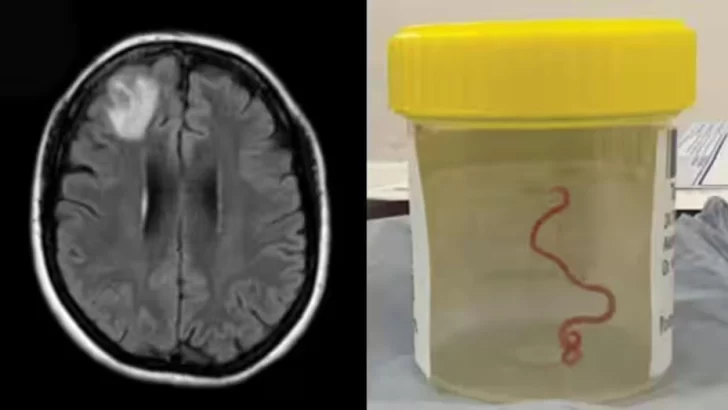

Una lombriz parásita usualmente encontrada en serpientes fue retirada "viva y coleando" del cerebro de una mujer, algo que no se había visto en los registros médicos, informaron el martes médicos australianos.

Era una lombriz de ocho centímetros llamada Ophidascaris robertsi, que según investigadores son parásitos comunes en canguros y pitones diamantina pero no en humanos.

"Este es el primer caso humano de una Ophidascaris en el mundo", afirmó el experto en enfermedades infecciosas Sanjaya Senanayake.

"Hasta donde sabemos, es también la primera vez que aparece en el cerebro de una especie de mamífero, humano o no", agregó.